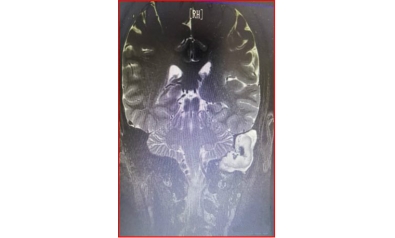

颅内肿瘤可微创治疗

随着医学发展日新月异,微创技术脱颖而出。内镜手术,尤其是颅底经鼻内镜手术大部分可以完全切除肿瘤,而且可显著全文…